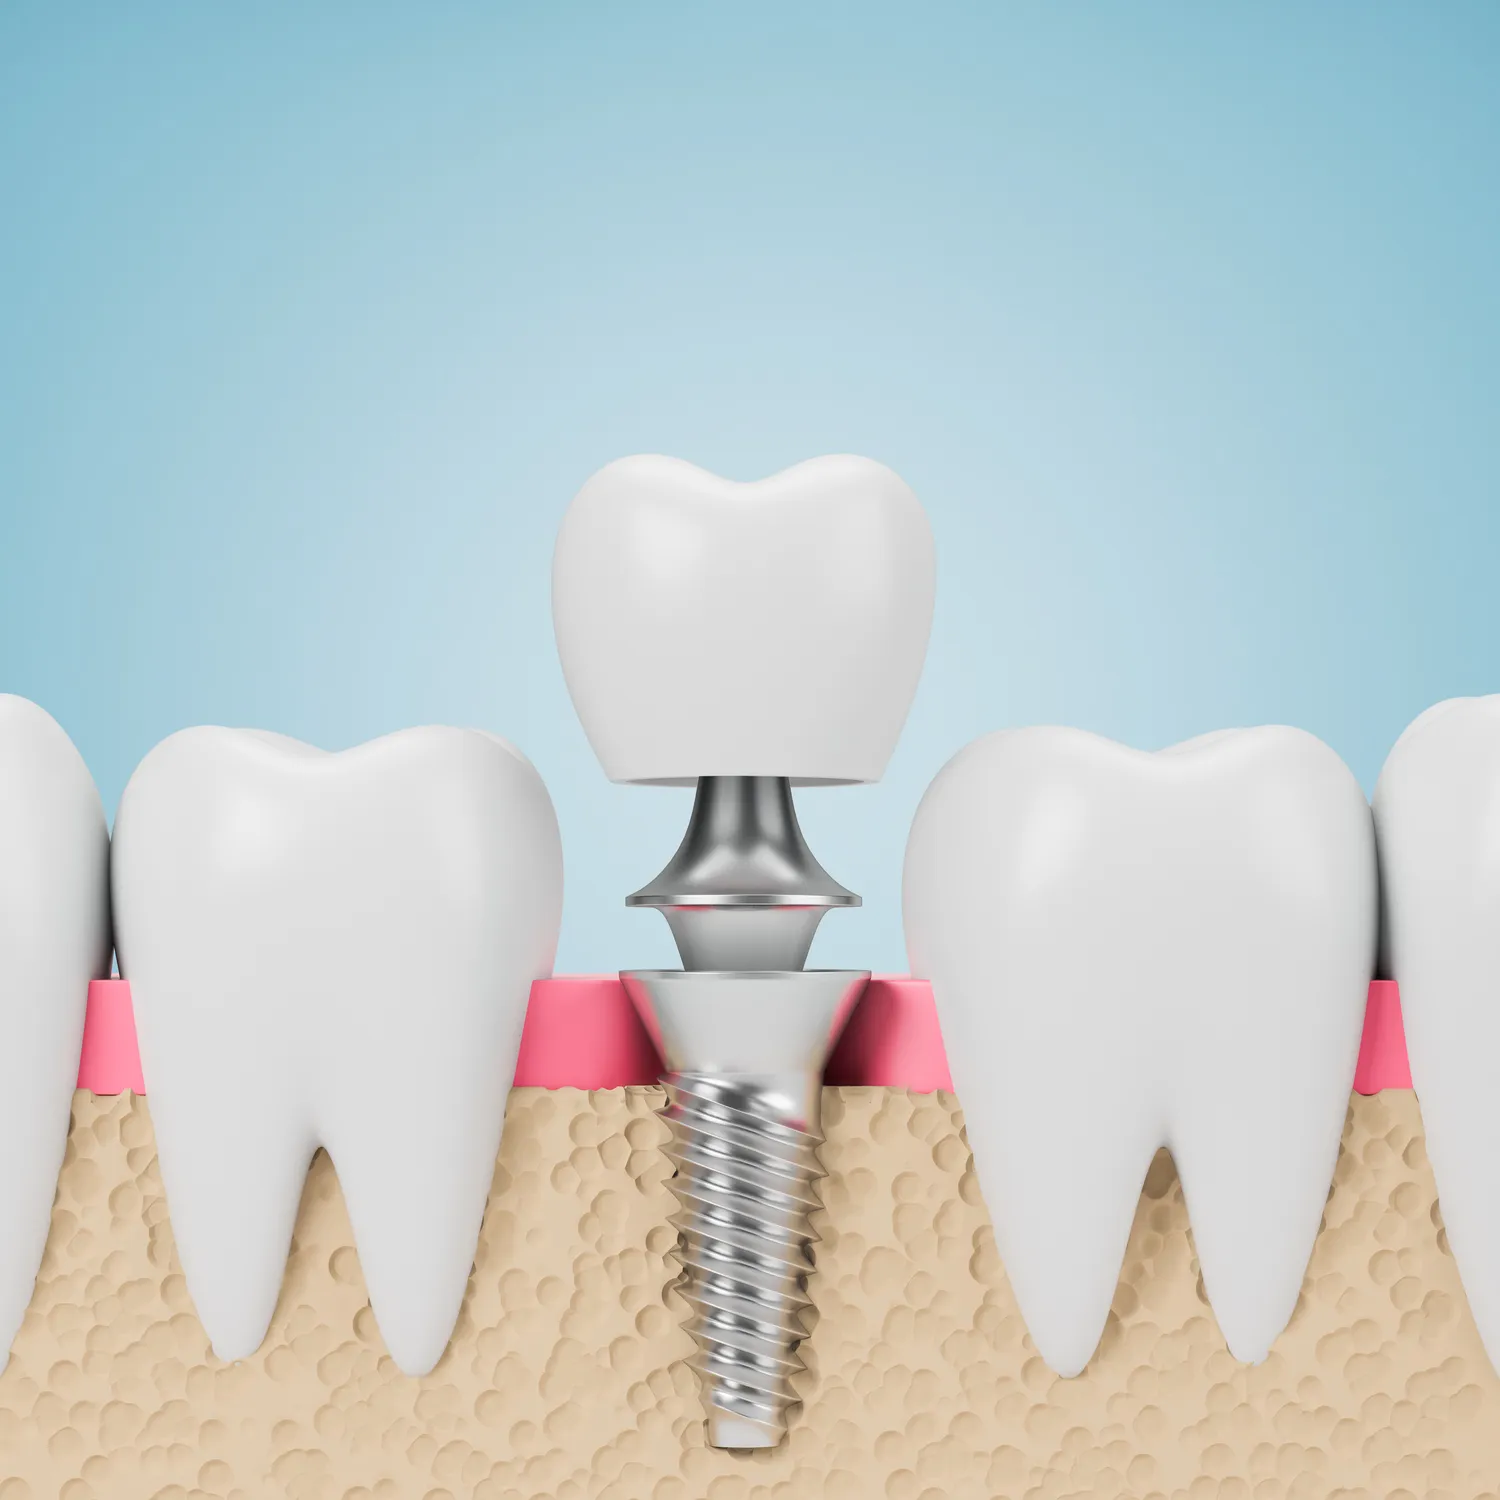

Jak wyglądają implanty zębowe?

Implanty zębowe to nowoczesne rozwiązanie stomatologiczne, które pozwala na odbudowę brakujących zębów. Istnieje kilka rodzajów implantów, które różnią się materiałem, kształtem oraz metodą umieszczania w kości. Najczęściej stosowane są implanty tytanowe, które charakteryzują się wysoką biokompatybilnością oraz trwałością. Tytan jest materiałem, który dobrze integruje się z kością, co zapewnia stabilność całej konstrukcji. Innym rodzajem są implanty ceramiczne, które cieszą się rosnącą popularnością ze względu na estetykę oraz mniejsze ryzyko alergii. W przypadku pacjentów z niewystarczającą ilością kości do osadzenia implantu, można zastosować różne techniki augmentacji kości, takie jak przeszczepy kostne czy użycie biomateriałów. Warto również wspomnieć o implantach miniaturowych, które są mniejsze i często stosowane w przypadkach, gdzie przestrzeń jest ograniczona.

Proces wszczepienia implantów zębowych składa się z kilku etapów, które wymagają staranności i precyzji ze strony stomatologa. Pierwszym krokiem jest dokładna diagnostyka, która obejmuje zdjęcia rentgenowskie oraz tomografię komputerową. Dzięki tym badaniom lekarz ocenia stan kości oraz planuje miejsce wszczepienia implantu. Następnie przeprowadza się zabieg chirurgiczny polegający na umieszczeniu implantu w kości szczęki lub żuchwy. Po wszczepieniu następuje okres gojenia, który może trwać od kilku tygodni do kilku miesięcy. W tym czasie implant integruje się z kością, co jest kluczowe dla jego stabilności. Po zakończeniu procesu gojenia można przystąpić do wykonania korony protetycznej, która zostanie zamocowana na implancie.